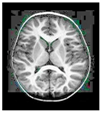

This work collects images from the Kaggle Brain MRI for Brain Tumor Detection dataset, which consists of 253 files with cancer and non-cancer brain images. The sample MRI is illustrated in Figure 2. The dataset has two folders: no tumor encoded as 0 and tumor as 1. The labeled data is more helpful in extracting the patterns from the MRI, which is used to predict the new images related output. The collected image consists of noise information that reduces the performance of brain tumor recognition accuracy. Therefore, image noise should be eliminated to improve the overall prediction efficiency.

Figure 2.

MRI samples Normal Brain MRI (Y1 to Y8) Benign tumor MRI (Y9 to Y15) Malignant tumor MRI (Y16 to Y21).